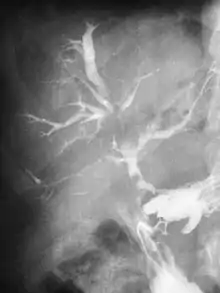

Нориця (також фістула) — патологічний або штучний канал, що зв'язує внутрішні органи чи патологічні осередки: зі шкірними покривами (зовнішні нориці) або між собою (внутрішні нориці). Загалом, з фістули виділяється рідкий вміст. Патологічний канал, так чи інакше, утворюється внаслідок омертвіння тканин, тому нориці є одним із видів змертвіння.

За своїм походженням розрізняють природжені фістули (аномалії розвитку плода), та набуті фістули, що утворилися внаслідок травми, операції, патологічного процесу (абсцес, флегмона, остеомієліт, парапроктит та інш.).

Нориці шлунково-кишкового тракту

Ці нориці, одні із найрозповсюдженіших за кількістю серед усіх фістул. Виникають як наслідок важких травм ШКТ(шлунково-кишкового тракту), після масивних та складних операцій. До них належать слинні нориці, нориці стравоходу, шлункові, тонкокишкові, панкреатичні, жовчеві, нориці товстого кишечника, параректальні, вроджені прикуприкові ходи. Окремо виділяють прямокишково-піхвові нориці.